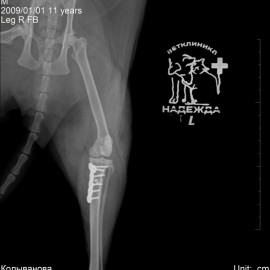

Рентгенологические снимки до операции.